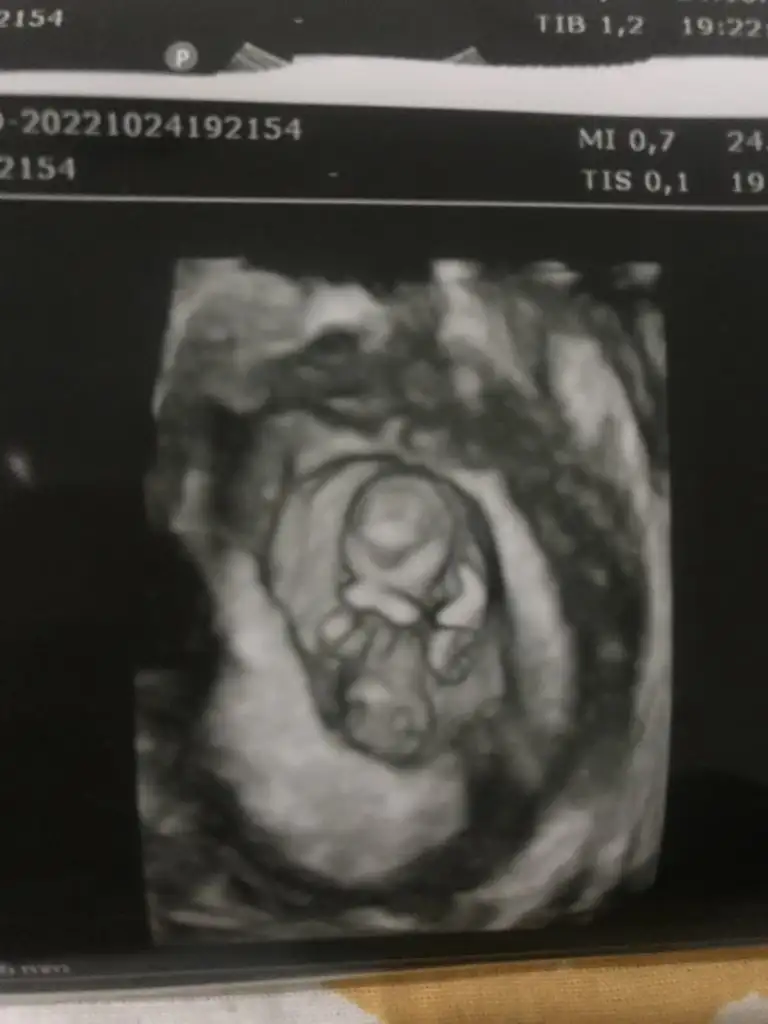

Bana da yorum yapabilir misiniz sizdeSelam Kızlarbir çok kişi gruplardan beni bilir. Yine yetiştim imdatlara

Bana da baksanızGeçen birkaç video izlemiştim. Genital kısımda 3 tane ince beyaz çizgi olunca kız diye anlatıyordu doktor. Bayağı örnek görmüştüm. Siiznki de öyle duruyor ama tabiki. Bu sadece bir tahmin allah gönlünğzden geçeni nasip etsin inşallah

Ne yazıkki sizinkinde net bir şekilde göremedim bir şey. Yanlış tahmindr bulunmak istememBana da baksanız